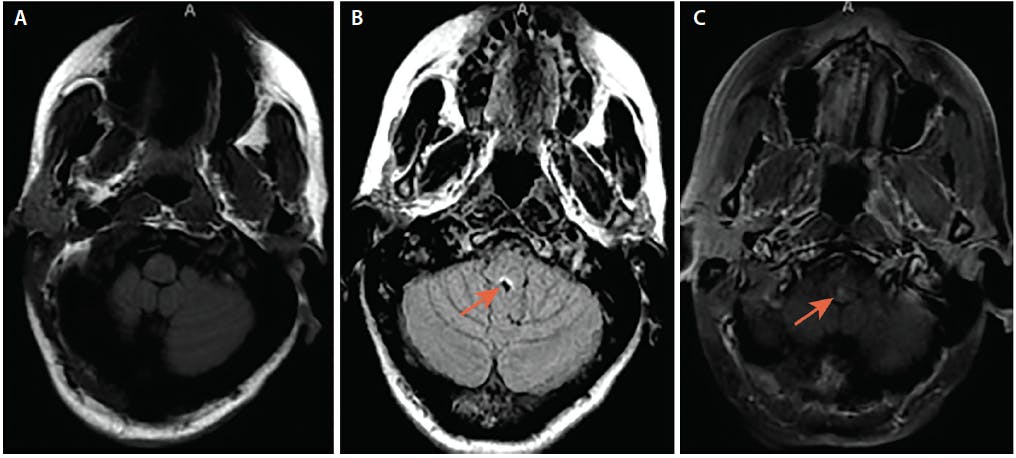

Brain MRI showed minimal scattered nonenhancing frontal lobe foci of demyelination and a focus of enhancement in the dorsal medulla suggesting active demyelination (Figure 2). MRI of the total spine showed increased T2 signal abnormality from the cervicomedullary junction to the spinal cord terminus.

Figure 2. Area Postrema Syndrome From Dorsal Medullary Lesion. Axial brain MRI (A) and axial fluid-attenuated inversion recovery

(FLAIR) MRI (B) show T2 hyperintense lesion in the dorsal medulla (B, arrow), and axial T1-post gadolinium MRI (C) shows enhancement

of the dorsal medullary lesion (arrow).

Figure 2. Area Postrema Syndrome From Dorsal Medullary Lesion. Axial brain MRI (A) and axial fluid-attenuated inversion recovery (FLAIR) MRI (B) show T2 hyperintense lesion in the dorsal medulla (B, arrow), and axial T1-post gadolinium MRI (C) shows enhancement of the dorsal medullary lesion (arrow).